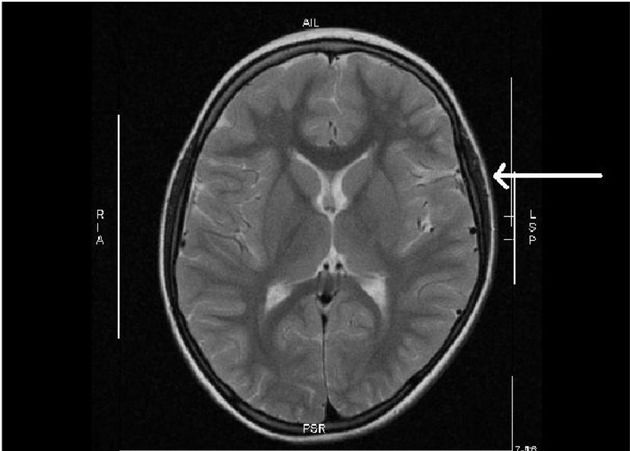

Ein Heilversuch mit Stammzellen bei Schlaganfall nach der Geburt wies den Weg

In einer kürzlich erschienenen Publikation hatte ein kleines Mädchen unter der Geburt einen Schlaganfall mit Halbseitenlähmung erlitten, obwohl es am Termin nach unauffälliger Schwangerschaft der Mutter mit normalen Apgar-Werten bei großem Kopfumfang (> 97. Perzentile) und Anzeichen einer starken Kopfverformung scheinbar gesund geboren worden war. Nach der Magnetresonanz-Tomographie des Schädels (MRT), die einen wegweisenden Befund ergab, wurde die Stammzellbehandlung aus Nabelschnurblut erfolgreich durchgeführt. "Zu unserer Überraschung war die Druckstelle am Gehirn durch die mechanische Kompression 5 Jahre nach der Geburt des Mädchens immer noch sichtbar", erinnert sich Prof. Arne Jensen. "Wir haben daraufhin unsere Datenbank gezielt durchsucht und festgestellt, dass bei Kombination von großem kindlichen Kopfumfang mit protrahierter Geburt oder Geburtsstillstand ein hohes Risiko für eine Hirnschädigung in der weißen Substanz besteht."